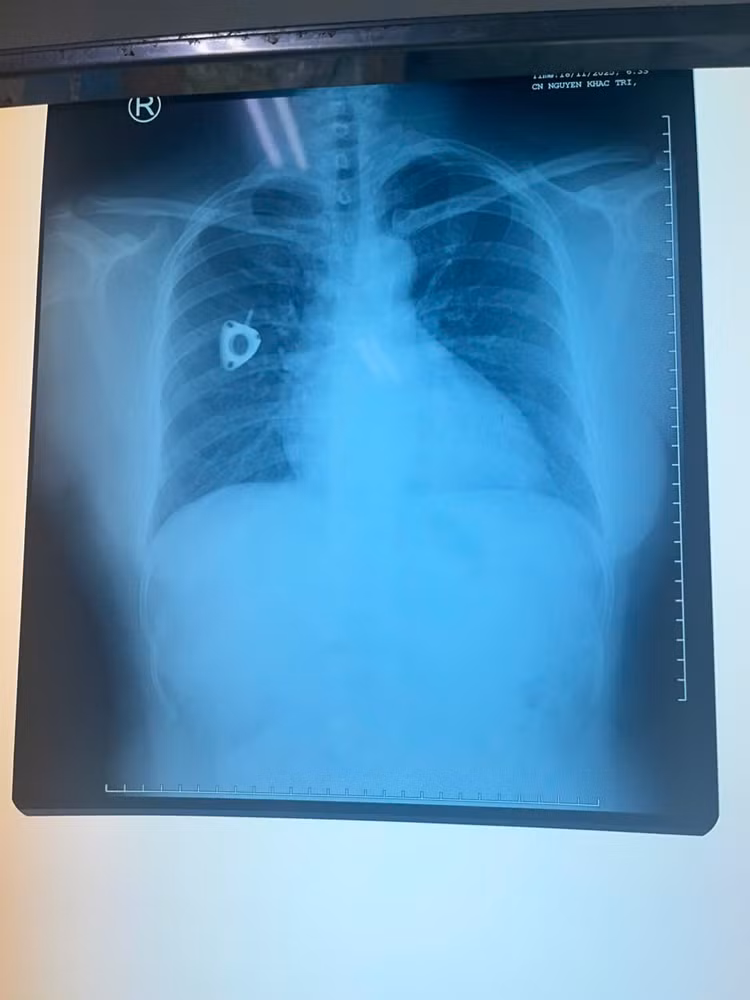

Hình ảnh X quang cho thấy dị vật ở động mạch phổi 2 bên.

Trong lần đi khám tầm soát tại một cơ sở y tế tư nhân, chị được chỉ định chụp CT ngực có tiêm thuốc cản quang, bác sĩ phát hiện hình ảnh một dị vật trong tim, nằm vắt ngang tại vị trí động mạch phổi hai bên.

Sau khi được tư vấn về khả năng cần thực hiện thủ thuật can thiệp lấy dị vật, bệnh nhân quay về bệnh viện đã điều trị ung thư trực tràng để tiếp tục thăm khám và được chụp Xquang ngực.